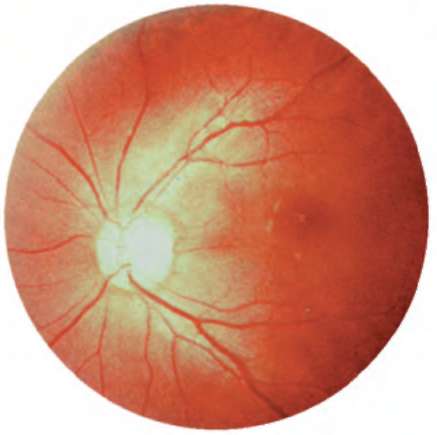

Рис. 12.1. Глазное дно. Норма